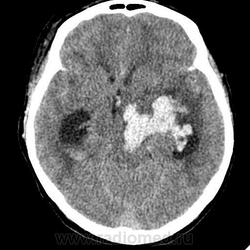

КТ головного мозга, кровоизлияние.

"Скорая" привезла женщину 75 лет, найденную на улице. На КТ направлена с д-зом: кома неясного происхождения. Вот такая картина на КТ.

Острое внутримозговое кровоизлияние с выходом крови в желудочки (боковые - сгустки преимущественно в левом + эффект седиментации с горизонтальным уровнем жидкость\жидкость в задних рогах; сгустки крови в третьем желудочке, кровь в четвертом). Значительное увеличение височных рогов боковых желудочков - гидроцефалия. Смешение срединных структур вправо, отек белого вещества перивентрикулярно слева.

Довольно большие кровоизлияния в стволе мозга (что объясняет тяжесть состояния).

Дифференциация серого и белого в-ва сохраняется, хотя субарахноидальное пространство не прослеживается - проявление масс-эффекта, начальный этап отека мозга.

Остается вопрос по слегка гиперденсному (относительно серго вещества) однородному фокусу в левой лобной доле... и по причине кровоизлияния. Что касается последнего могу предположить патологию базилярной артерии (разрыв аневризмы?)... правда не вижу что-то крови в цистернах основания черепа.

Я написала отек мозга, острое массивное (около 100 мл только внутримозговое) смешанное кровоизлияние слева + в стволе, с прорывом и гемотампонадой желудочков, выраженной латеральной дислокацией (13 мм), менингиома? лобного полюса слева. Убедительных данных за опухоль, давшую кровоизлияние, не вижу, хотя такая мысль тоже была.  Контрастировать такую пациентку никто не будет, агонизирующая(.

У, сколько всего написано. Пока не пришла Nela, поучаствую и я. 1. Кровоизлияние в ткань мозга, а не в опухоль: а)не видно ткани опухоли; б) неясна первичная локализация опухоли (левые базальные ядра?!); в)нет перифокального отека вокруг предролагаемой опухоли, г) при опухолях прорывы в желудочки - редкость; 2) к поперечной дислокации добавил бы безесловную аксиальную: даже цистерна моста сужена, не говоря уже про обходную-четверохолмную и другие; 3) менингиома в левой лобной области, на мой взгляд, сомнительна (кстати, покажите ее пожалуйста), ИМХО - "игра" плотностей;  4) ///метастазы в сосудистые сплетения/// - это очень круто, но они не дали бы внутримозгового кровоизлияния, как и ///плексуспапилома///.

Массивное медиальное кровоизлияние с прорывом в желудочки. Кровоизлияние в ствол. Признаки вклинения. В лбу может что-то и есть, но это не принципиально. А может быть и отечные извилины. Смущает, что нет масс-эффекта.

Про отек: субарахноидальных щелей совсем нет, по белому веществу и в стволе снижение плотности, извилины утолщены, серое вещество на этом фоне выглядит более светлым, толстым, подушкообразным.

Причина таких кровоизлияний, как правило, гипертензия и атеросклероз.

Кровоизлияние не связанное с объемным образованием, "гипертоническое", основной массой - в области базальных ядер, кровоизлияние в ствол мозга, кома ясного происхождения :) А менингиома менигниомой, не мешает, так сказать.  Отека мозга здесь небольшой, больше выражено набухание.